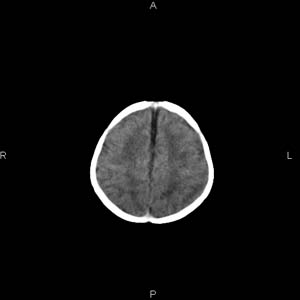

患者男,27天,出生后正常,今天中午在母亲怀里抱着吃奶在放下睡觉时发现后枕部慢慢出现一包块,来查头颅ct。无外伤史。包块内ct值47-51hu。请大家讨论。

支持脑膜脑膨出,双侧侧脑室三角区周围脑白质对称性低密度影,考虑缺血缺氧性脑病或肾上腺性脑白质营养不良。